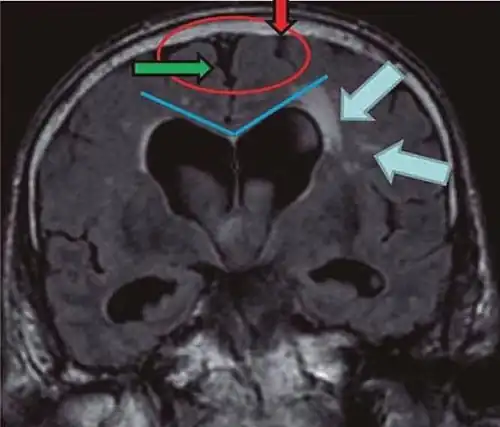

• Imaging from magnetic resonance imaging (MRI) or computed tomography (CT) is needed to demonstrate enlarged ventricles and no macroscopic obstruction to cerebrospinal fluid flow. Imaging should show an enlargement to at least one of the temporal horns of lateral ventricles, and impingement against the falx cerebri resulting in a callosal angle ≤ 90° on the coronal view, showing evidence of altered brain water content, or normal active flow (which is referred to as "flow void") at the cerebral aqueduct and fourth ventricle.

Typical imaging findings in normal pressure hydrocephalus versus brain atrophy.[21]

Normal pressure hydrocephalus Brain atrophy

Preferable projection Coronal plane at the level of the posterior commissure of the brain.

Modality in this example CT MRI

CSF spaces over the convexity near the vertex (red ellipse ) Narrowed convexity ("tight convexity") as well as medial cisterns Widened vertex (red arrow) and medial cisterns (green arrow)

Callosal angle (blue V) Acute angle Obtuse angle

Most likely cause of leucoaraiosis (periventricular signal alterations, blue arrows ) Transependymal cerebrospinal fluid diapedesis Vascular encephalopathy, in this case suggested by unilateral occurrence